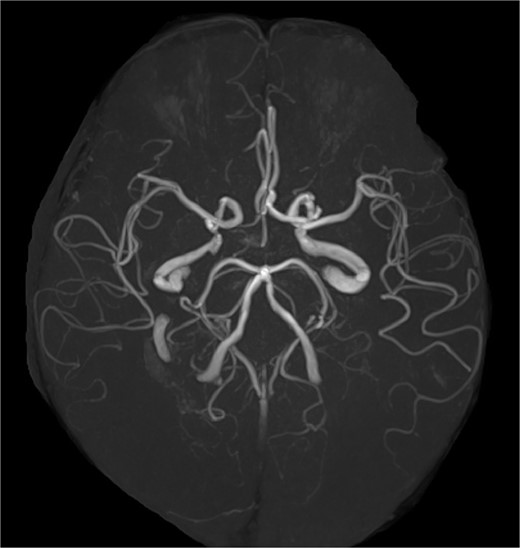

A 68-year-old male patient had undergone distal aortic arch replacement with lateral thoracotomy 13 years earlier for chronic distal aortic arch dilatation of a type B aortic dissection of unknown onset. Three years ago, a saccular aortic aneurysm, probably arising from the anastomosis site, was observed; as it had a tendency to dilate over time, surgical intervention to prevent rupture was decided upon. Although the patient was scheduled for TEVAR, his anatomy showed an ILVA with its origin in a position of forced occlusion due to the stent graft landing in zone 2 (Fig. 1a). In most cases, the entry of the ILVA under the transverse process of the vertebra is at the fifth cervical vertebra; however, in this case, the entry was from the sixth cervical vertebra (Fig. 1b). Magnetic resonance angiography showed poor delineation of the bilateral posterior communicating arteries, and the Willis arterial circle was likely nonfunctional, suggesting that revascularization of the ILVA would be beneficial for neurological prognosis (Fig. 2).

Magnetic resonance angiography image. The Willis arterial circle is incomplete.